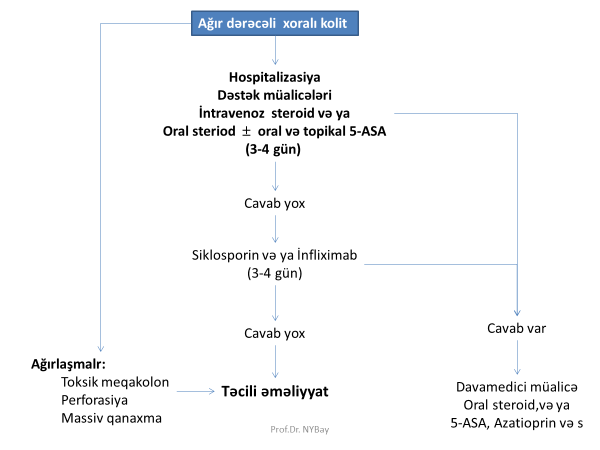

İBX müalicəsində hansı dərmanlar istifadə olunur?

- aminosalisilatlar: mesalamin, sulfasalazin

- immunosuppressorlar: azatioprin, steroid (prednizolon, hidrokortizon, budesonid)

- antibiotiklər: metronidazol, siprofloksin

- infliksimab

İBX kəskinləşməsində ilk olaraq hansı dərmandan istifadə olunur?

Mesalamin və/və ya steroidlər

Steroid müalicəsinə cavab verməyən kəskinləşmələrdə nə edilir?

İmmunosupressor və ya infliksimab və ya cərrahi müalicə.

Azatioprin ilə infliksimab təsir effektinə görə necə fərqlənir?

İnfliksimab effektini erkən (günlər sonra), azatioprin isə gec (həftələr sonra) göstərir.